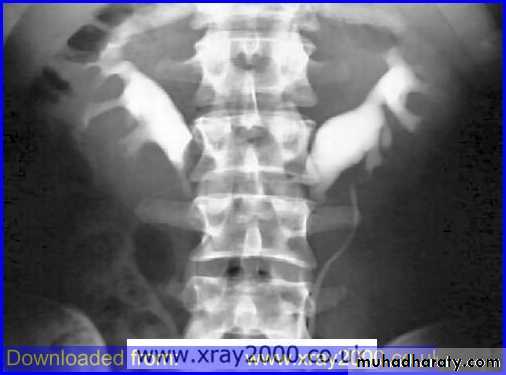

Poly cystic disease

Adult type

Present after the third decade of life , Familial.

Renal parenchyma is replaced by numerous cysts containing fluid , The cysts are of variable size ,

Clinically renal colic, loin mass , heamaturia and hypertension, Renal tissue interposed between the cysts after time dssimcted ended with renal failure

Almost bilateral.

IVU

Large kidney .

Lobulated out-line.

Distortion of pelvi- calyceal system depend on cyst size, number and position.

In advanced cases there is elongation and stretching of minor and major calyces ( spider leg).

In advanced cases IVU shows non-functioning kidney .